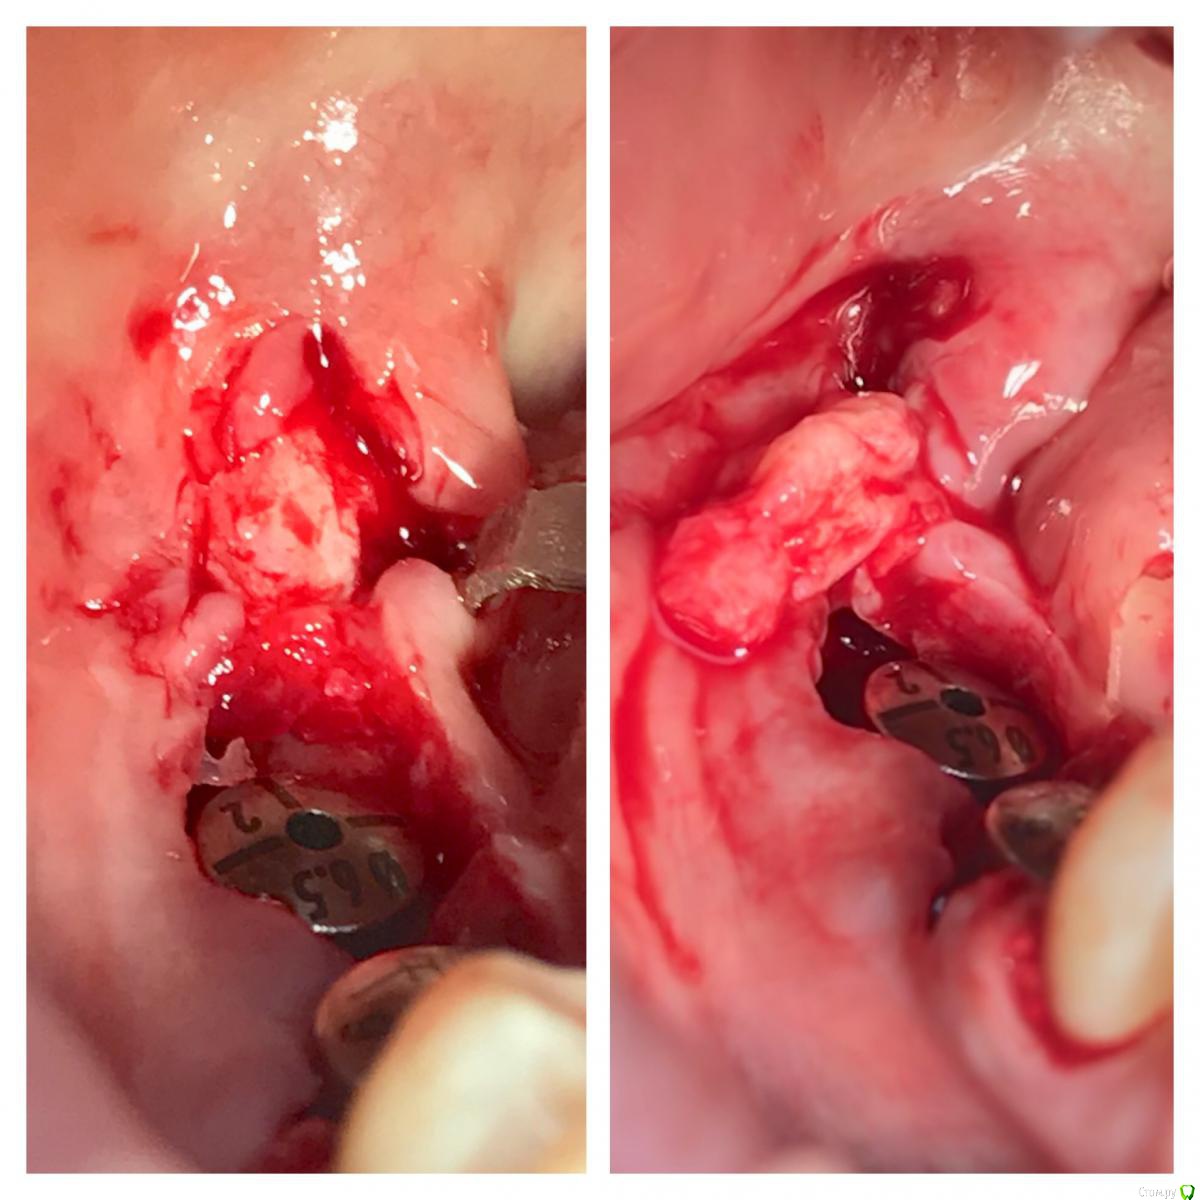

колесников Опубликовано 9 мая, 2017 Автор Поделиться Опубликовано 9 мая, 2017 Да,"приберечь " это про низ. Бугор берётся расщеплённый,не полностью, хорошо регенерирует . Через 4 недели можно брать снова. Травма у нас местно есть в любом случае,кератинизированая расщеплённая десна регенерирует очень хорошо и малоболезненно. Как пример фото разместил :в первом случае со "змейки " я снял швы через неделю и простился,во втором ,где свободный лоскут,остатки его убрал через 3 недели и ещё неделя наблюдений.На фото расщеплённый бугор. На последнем -с выделенным сст. Ссылка на комментарий

колесников Опубликовано 5 июля, 2019 Автор Поделиться Опубликовано 5 июля, 2019 Ещё раз о ретировалось лоскуте . Из ретромолярной зоны на н/ч перекинут Вестибулярно к 7ке и с неба перекинут Вестибулярно уже для верхней 7ки. Оба случая значительный дефект вестибулярной стенки,одномоментная имплантация,грануляции. Получается хороший стабильный и плотный каркас. 1 зона. 1 Ссылка на комментарий